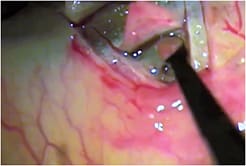

Canaloplasty appears to improve the outflow and drainage into the collector channels once the aqueous fluid percolates outward through the internal trabecular meshwork. In this procedure, a scleral dissection extends to the Canal of Schlemm. The surgeon passes a 250-μm catheter with a lumen and fiberoptic light circumferentially 360 degrees around the canal. The catheter introduces a prolene suture tied to the tip that withdraws back through the canal. Then, the surgeon cuts the suture from the catheter and tightens it over a window of Descemet’s membrane approximately 500-μm in width. Finally, the surgeon amputates the deep scleral flap and sutures down the superficial flap.

The surgeon passes a 250-μm catheter with a lumen and fiberoptic light (top right) circumferentially 360 degrees around the Canal of Schlemm.

COURTESY ELLEX MEDICAL